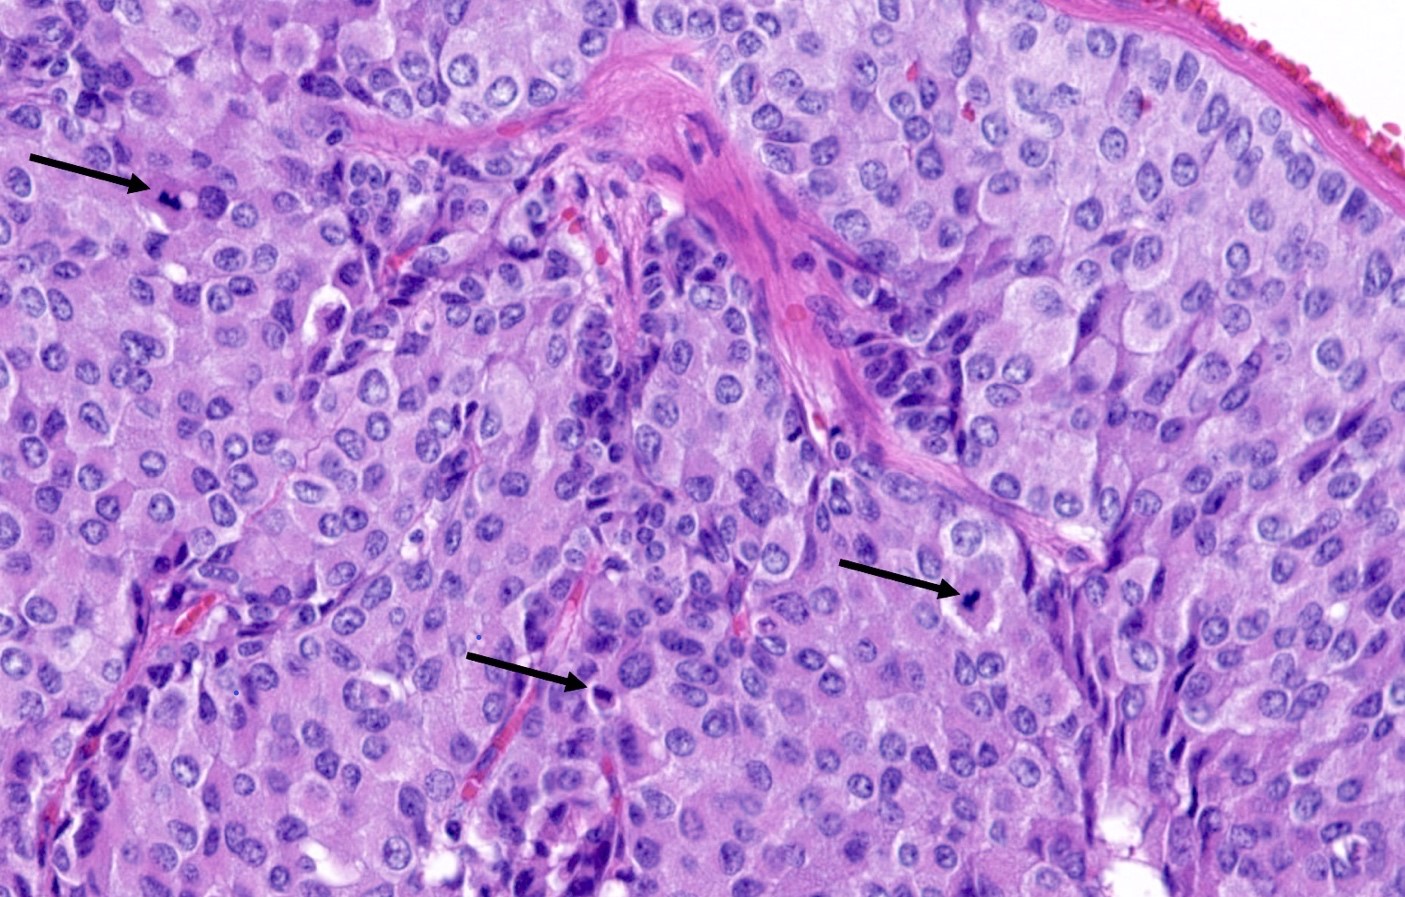

Contributed by Philippe Joubert, M.D., Ph.D.

- A patient undergoes a lobectomy for a well circumscribed nodule. On H&E slide, the tumor exhibits a well differentiated neuroendocrine morphology and you observe the histologic features presented in the image. Which of the following statements is true?

B. It is defined as a well differentiated neuroendocrine tumor with 2 - 10 mitoses per 2 mm² or foci of necrosis. The picture shows a carcinoid lung tumor with a classical neuroendocrine morphology and 2 mitoses in 1 high power field. Even though the whole tumor is not presented here, the presence of 2 mitoses is sufficient for an atypical carcinoid diagnosis.

While Ki67 proliferation rate is frequently > 10% in atypical carcinoids, this feature is not part of the diagnosis (A). C is nearly exact but mitotic count is not made on 1 high power field. Finally, the diagnosis can be suggested on small samples but a thorough examination of a resection specimen is necessary to confirm an atypical carcinoid diagnosis (D).